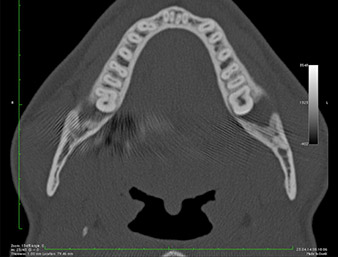

In der 3D-Aufnahme (digitales Volumentomogramm) war ersichtlich, dass sich der Wurzelrest weit disto-kaudal im Übergang vom horizontalen zum aufsteigenden Anteil des Unterkiefers befand (Abb. 2).

DVT-Darstellung

Abb. 2: Transversale DVT-Darstellung des Wurzelrests im retromolaren Raum

Unser Patient besaß anamnestisch gute Voraussetzungen (Nichtraucher, 26 Jahre) für einen erfolgreichen Eingriff. Wegen des Hinweises auf enge Lagebeziehung des Wurzelrestes zum N. alveolaris inferior in der Panoramaschicht-Aufnahme wurde zusätzlich eine digitale Volumentomografie erstellt (6).

Die gefundene, sehr enge Lagebeziehung erforderte eine präzise und schonende Osteotomie. Hier sprechen klinische Beobachtungen und Vergleichsstudien für die seit Ende der 1990er Jahre verfügbare Piezochirurgie (9-11). Durch die charakteristische Mikro-Oszillation dieser Systeme lässt sich Knochen gezielt abtragen, wodurch eine minimal invasive Präparation ermöglicht wird.